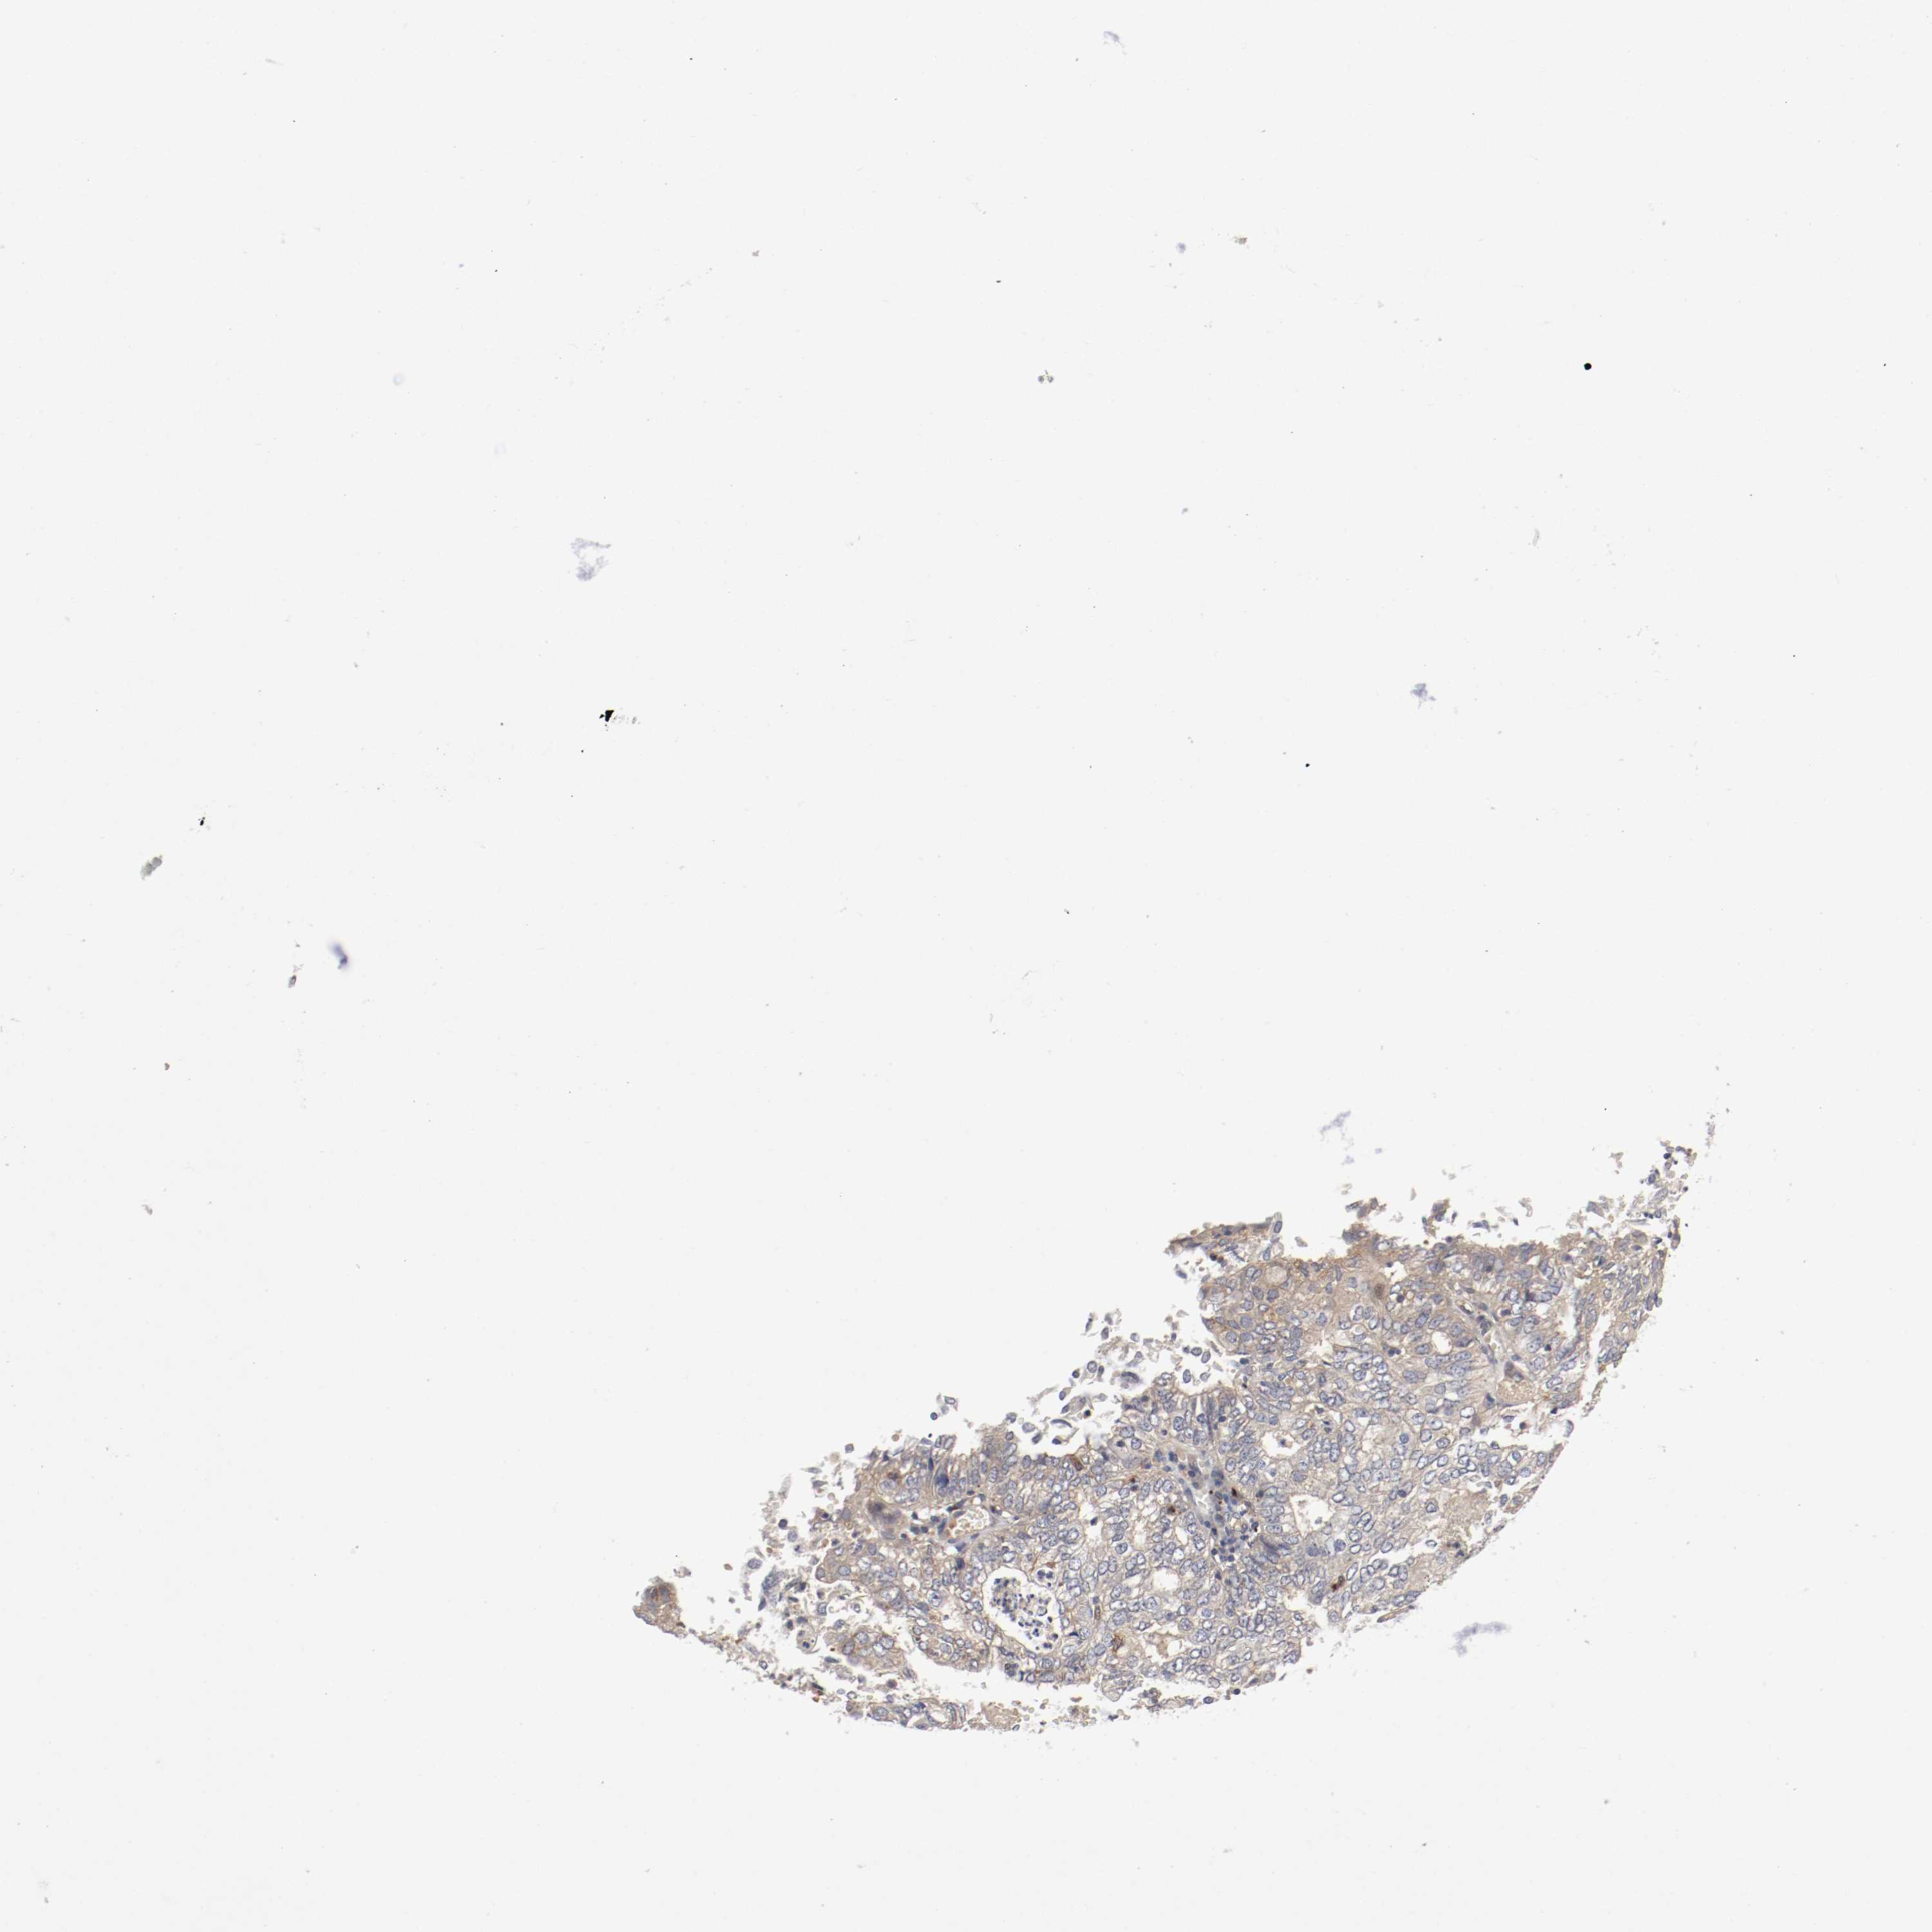

ENDOMETRIAL CANCER - Protein expressioni

A mouse-over function shows sample information and annotation data. Click on an image to view it in a full screen mode. Samples can be filtered based on level of antibody staining by selecting one or several of the following categories: high, medium, low and not detected. The assay and annotation is described here.

Note that samples used for immunohistochemistry by the Human Protein Atlas do not correspond to samples in the TCGA dataset.

Antibody stainingi

Antibody staining in the annotated cell types in the current human tissue is reported as not detected, low, medium, or high, based on conventional immunohistochemistry profiling in selected tissues. This score is based on the combination of the staining intensity and fraction of stained cells.

Each image is clickable and will lead to virtual microscopy that enables deeper exploration of all samples and also displays staining intensity scores, fraction scores and subcellular localization as well as patient and tissue information for each sample.

Antibody HPA005131

Staining

High

Medium

Low

Not detected

Intensity

Strong

Moderate

Weak

Negative

Quantity

>75%

75%-25%

<25%

None

Location

Nuclear

Cytoplasmic/membranous

Cytoplasmic/membranous,nuclear

Adenocarcinoma, NOS

Neoplasm, malignant, NOS